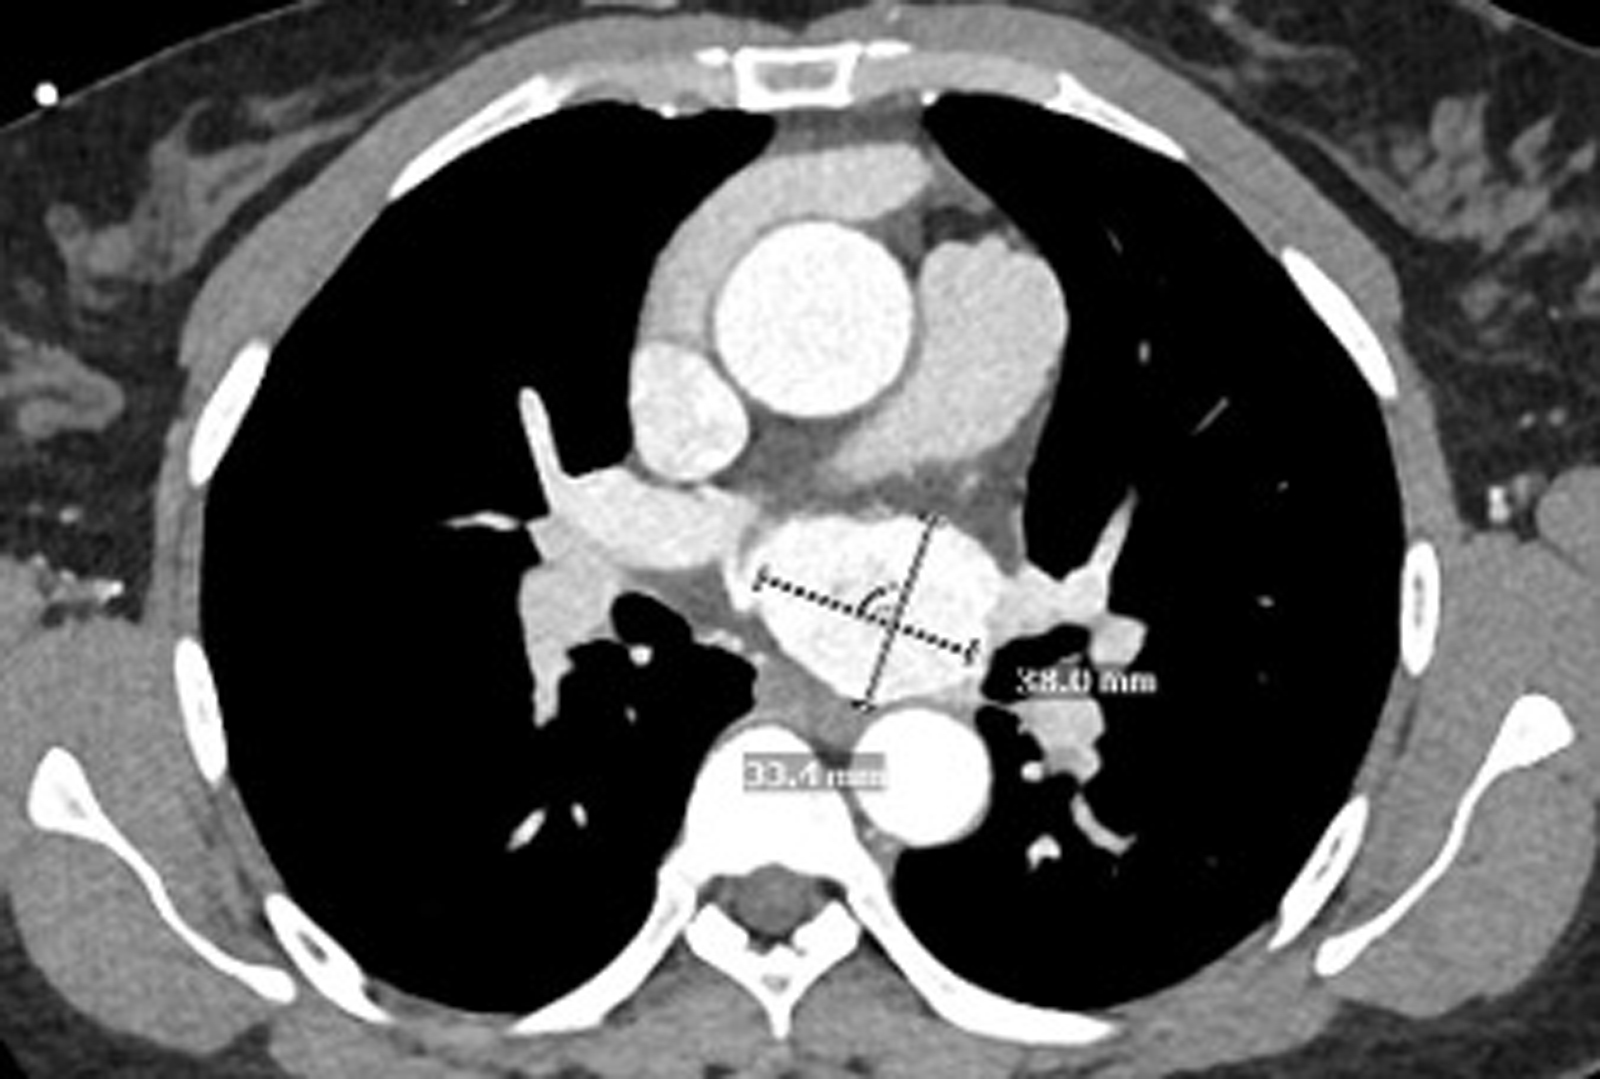

Upon further imaging, Dr. Bizekis confirmed attachment of the tumor to the left atrium, warranting the involvement of cardiac surgery. Coronary CT angiography also revealed external compression of the left atrium and upper pulmonary vein—further complicating the case.

Preoperative CTA showing the tumor location relative to the spine, aorta, and pulmonary veins. Source: NYU Langone Health